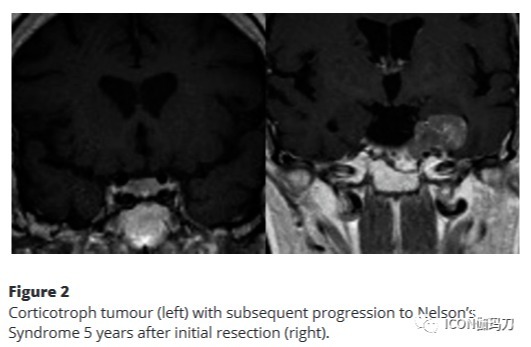

垂体瘤的诊断评估和预后仍然是一个重大的临床挑战。虽然有公认的临床和组织病理学标志物可以帮助预测不良行为,但一些表面上不明显的肿瘤会进展为进袭性疾病。在最近包含171例垂体瘤的队列中,14例进展为临床进袭性疾病。其中7例组织学类型为“低风险”,Ki67<3%;通常与良性行为相关(lenders等,2021b)(图2)。相反,一些就诊时具有不良特征的肿瘤可能在许多年内不会进展。在这种情况下,尚不清楚疾病进展的决定因素,需要进一步研究。

图2促肾上腺皮质激素细胞瘤(左)在初次切除术后5年进展为Nelson综合征(右)。